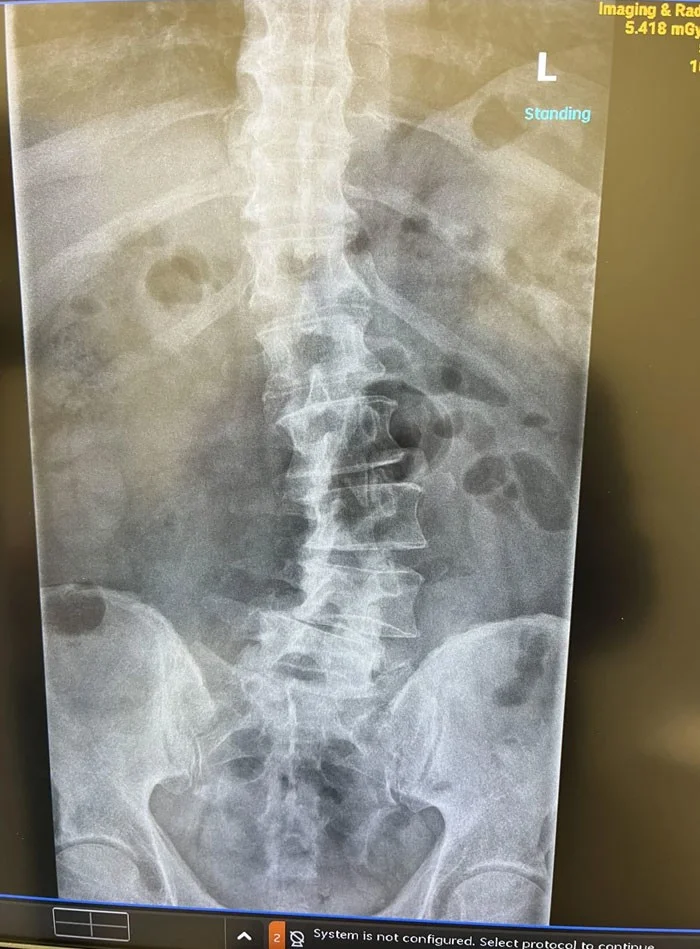

16. «Мой рентгеновский снимок после перелома спины»

25. «Папа сказал, что у него побаливает спина»